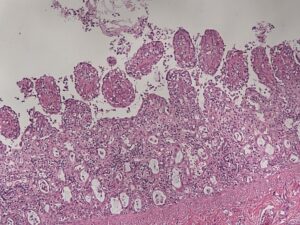

Abb. 1: Dünndarm: deutliche Zottenatrophie und -fusion mit Nekrosen der Kryptenepithelien (HE-Färbung)

Bildquelle: Laboklin

Histologisch findet man klassische Läsionen wie Nekrosen der Kryptenepithelien, verkürzte und atrophierte Zotten (Abbildung 1), Riesenzellbildung als ein Anzeichen für Kryptenregeneration und lymphatische Depletionen. Teilweise können auch intranukleäre Viruseinschlusskörperchen beobachtet werden (Carman und Povey, 1985; Decaro und Buonavoglia, 2012, Osterhaus et al., 1980).